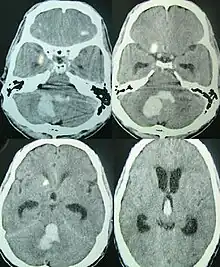

![]() | |

| CT scan of a spontaneous intracerebral bleed, leaking into the lateral ventricles | |

Intraparenchymal hemorrhage can be recognized on CT scans because blood appears brighter than other tissue and is separated from the inner table of the skull by brain tissue. The tissue surrounding a bleed is often less dense than the rest of the brain because of edema, and therefore shows up darker on the CT scan.[30] The oedema surrounding the haemorrhage would rapidly increase in size in the first 48 hours, and reached its maximum extent at day 14. The bigger the size of the haematoma, the larger its surrounding oedema.[31] Brain oedema formation is due to the breakdown of red blood cells, where haemoglobin and other contents of red blood cells are released. The release of these red blood cells contents causes toxic effect on the brain and causes brain oedema. Besides, the breaking down of blood-brain barrier also contributes to the odema formation.[13]